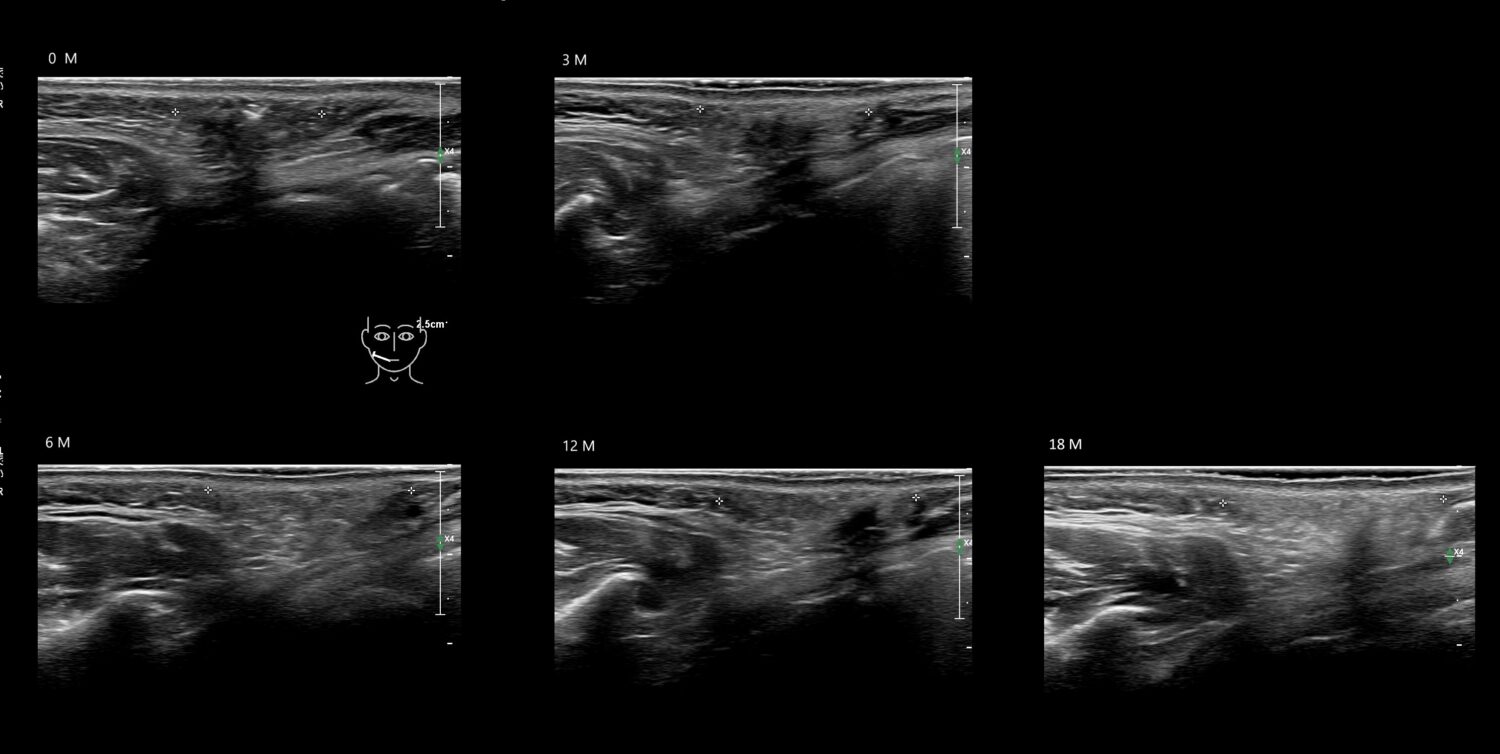

Fillers

Draw in the image on the right where the fillers are located. To check if your answer is correct, please click on the secondary image.